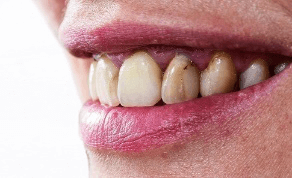

虫歯や事故など何らかの理由で神経を抜いた歯は、時間がたつと明度が下がり茶色~黒色に変色してきます。

原因は神経があることで健康だった歯が、神経がなくなることで血液の供給が止まり、象牙質のたんぱく質が変色したり、細菌に感染するなどの理由でくすんできます。

ちょうど枯れ木が茶色く変色してくるのと同じです。また歯の神経は歯の先端付近まで細い神経が通っており、神経を取る際に神経組織の取り残しや、出血した血が残っていると変色の原因になります。特に血液成分は鉄分が多く含まれていますので、血液が残っていると黒く変色してきます。

神経を取ってしまって変色した歯は、通常のホワイトニングでは白くなりにくく、また色戻りもしやすくなっています。変色の原因が神経組織の取り残しや血液成分による場合、その原因を取り除かない限り白くなりません。